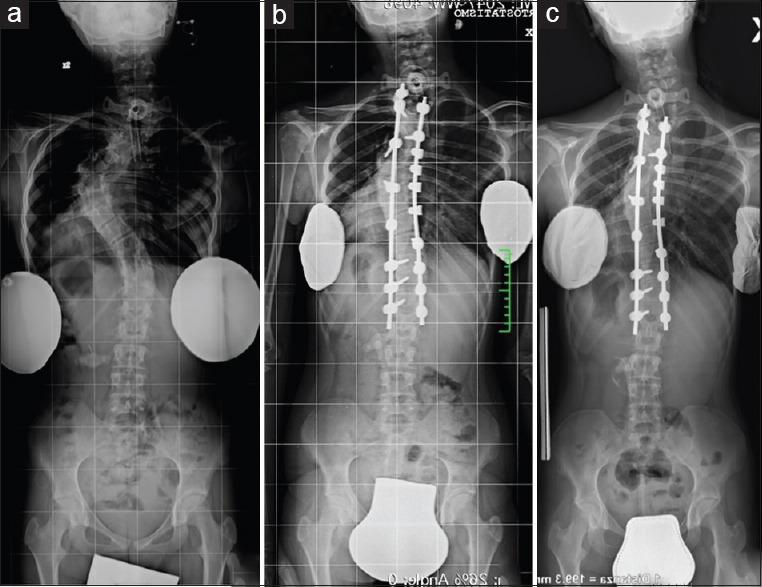

Ten patients were diagnosed with scoliosis in neurofibromatosis type I aged between 8 and 25 years, Cobb angle of the thoracic curve >45°, and minimum follow-up (FU) of 1 year and treated with posterior-only approach with third-generation high-density instrumentations. Radiographic measurements were performed on the coronal and sagittal planes. Nonparametric tests (Friedman test and Wilcoxon test) were applied to evaluate the reducibility of the preoperative curve (T0), the postoperative surgical correction (T1), and its maintenance on FU.

Statistics showed results compared to those evaluated in the literature with a combined approach regarding surgical correction and its maintenance on FU. On T1, a median correction of 53.5% of the scoliotic curve and of 33.7% of the thoracic hyperkyphosis was observed. On FU, the correction was maintained. A global improvement in balance was appreciated. The curves, despite rigid, showed a relative reducibility to bending tests and traction. No significant complications occurred.

The posterior-only approach produces a satisfactory correction of the dystrophic neurofibromatosis scoliosis if associated with the use of high-density third-generation instrumentations. We are confident in recommending posterior-only approach in dystrophic neurofibromatosis scoliosis with coronal curves till 110° and coexisting thoracic kyphosis till 80°.

10例年龄在8至25岁之间、胸弯Cobb角>45°且最短随访1年的Ⅰ型神经纤维瘤病脊柱侧弯患者,采用第三代高密度器械单纯后路手术治疗。在冠状面和矢状面上进行影像学测量。应用非参数检验(Friedman检验和Wilcoxon检验)评估术前侧弯(T0)的可矫正性、术后手术矫正(T1)及其在随访期的维持情况。

统计学结果显示,与文献中联合手术方法评估的手术矫正及其在随访期的维持情况相比,在T1时,观察到脊柱侧弯曲线中位数矫正53.5%,胸椎后凸矫正33.7%。在随访期,矫正得以维持。整体平衡得到改善。尽管侧弯僵硬,但在弯曲试验和牵引时显示出相对可矫正性。未发生明显并发症。

如果联合使用第三代高密度器械,单纯后路手术可对营养不良型神经纤维瘤病脊柱侧弯产生满意的矫正效果。我们有信心推荐对冠状面弯曲达110°且并存胸椎后凸达80°的营养不良型神经纤维瘤病脊柱侧弯采用单纯后路手术。